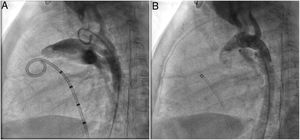

Both patients with history of previous PDA closure were successfully treated. The first was a seven year-old child who had a coil implanted at age three. The procedure was technically difficult, requiring a guidewire capture using a snare catheter to go through the residual PDA (Figure 11), and an Amplatzer duct occluder II 3x4 mm device was implanted successfully. The second patient was a 19 month-old child with PDA and pulmonary hypertension after an unsuccessful surgical ligation. In this case, sizing with a Tyshak balloon was required before implanting an Amplatzer duct occluder II 3x4 mm device (Figure 12).

A coil was used in 139 patients (62.9%) and an Amplatzer duct occluder was used in 79 patients (35.7%). In the three remaining patients (1.4%), an Amplatzer vascular plug was used for closure (Figures 2-8). Despite the higher overall rate of coil device implantation, Amplatzer duct occluder usage had been clearly superior since 2011. Of all coil devices used, 55% were either 4x4 mm or 5x4 mm in size (Figure 9), and of all duct occluder devices used, 72% were Amplatzer duct occluder I 6x4 mm or 8x6 mm in size (Figure 10), which correlates to the fact that most patients who were referred had small- to moderate-sized ductus arteriosus. While ADO II and ADO II AS devices can be implanted in a retrograde fashion, only on two occasions was a retrograde deployment performed (both ADO II devices).